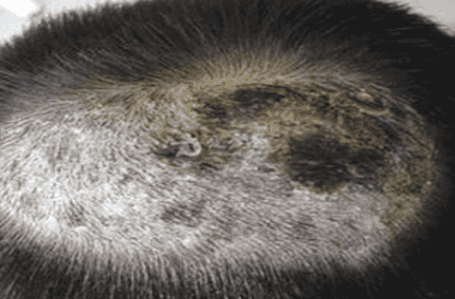

1、头癣。因为真菌感染引起的皮肤病,有传染性,头上容易出现头皮屑增多,发痒,脱发等情况。小孩子也比较常见,无束发状,严重的会出现斑秃的症状,一般出油比较少,危害主要就是痒,起皮,不舒服和斑秃。